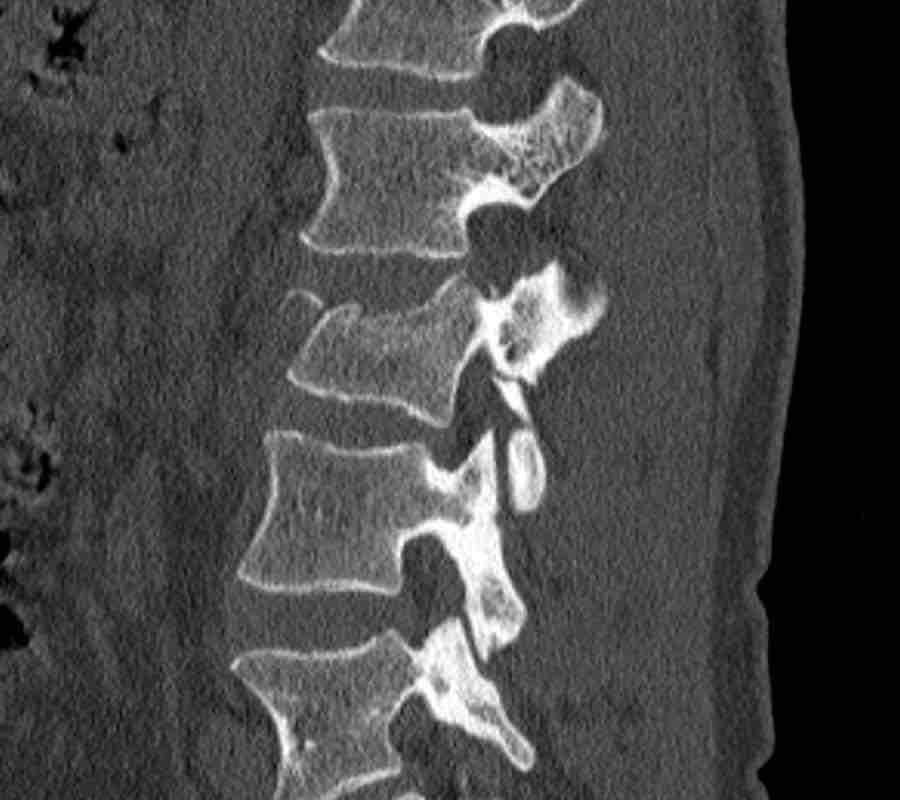

What is the highest AO-type of injury?

Findings

- No C or B injury.

- Fractures of the vertebral body with involvement of both endplates (1+1 points) and posterior wall (2 points).

- In the coronal plane, a sagittal course of the fracture is seen, which is common in burst fractures.

- Bulging of the posterior wall without any other signs of dislocation is the result of the burst fracture.

Therefore no C injury.

Conclusion

Injury type A4